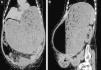

Ingresa en nuestro servicio por cuadro de dolor abdominal de instauración brusca, acompañado de vómitos y ausencia de ventoseo. En la exploración física presentaba gran distensión abdominal, timpanismo y datos de irritación peritoneal. Analíticamente se objetivó acidosis metabólica compensada, siendo el hemograma, coagulación, PCR y bioquímica básica normales. La radiografía de abdomen ponía de manifiesto una gran dilatación gástrica (fig. 1), por lo que se solicitó TAC abdominal urgente (fig. 2A y B) donde se observó distensión gástrica secundaria a estenosis pilórica completa y neumoperitoneo, sin objetivar claro punto de perforación.

Imágenes de TAC abdominal. A) Corte coronal; B) Corte sagital: estómago muy distendido, con contenido alimenticio y aire, sin observar paso del mismo hacia duodeno, en relación con estenosis pilórica conocida. Neumoperitoneo en abdomen superior, y pequeña cantidad de líquido libre perigástrico.